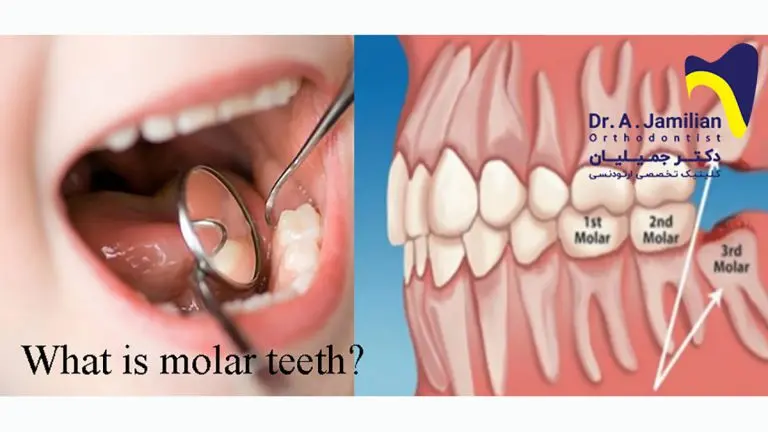

Was sind Backenzähne?

Backenzähne, auch Molaren genannt, sind die hinteren Zähne im Gebiss. Sie sind größer und breiter als Schneidezähne und Eckzähne und haben eine flache Kaufläche, die für das Zerkleinern von Nahrung konzipiert ist. Sie befinden sich hinter den Eckzähnen und sind in zwei Gruppen unterteilt:

Dauerbackenzähne

Die Dauerbackenzähne, auch als bleibende Molaren bezeichnet, ersetzen die Milchbackenzähne. Es gibt insgesamt zwölf Dauerbackenzähne, sechs im Oberkiefer und sechs im Unterkiefer. Die ersten Dauerbackenzähne, auch als sechsjahresmolaren bezeichnet, erscheinen zwischen dem fünften und siebten Lebensjahr. Diese Zähne sind besonders wichtig, da sie die Lücke zwischen den Milchzähnen schließen und für eine korrekte Ausrichtung der anderen Zähne sorgen.